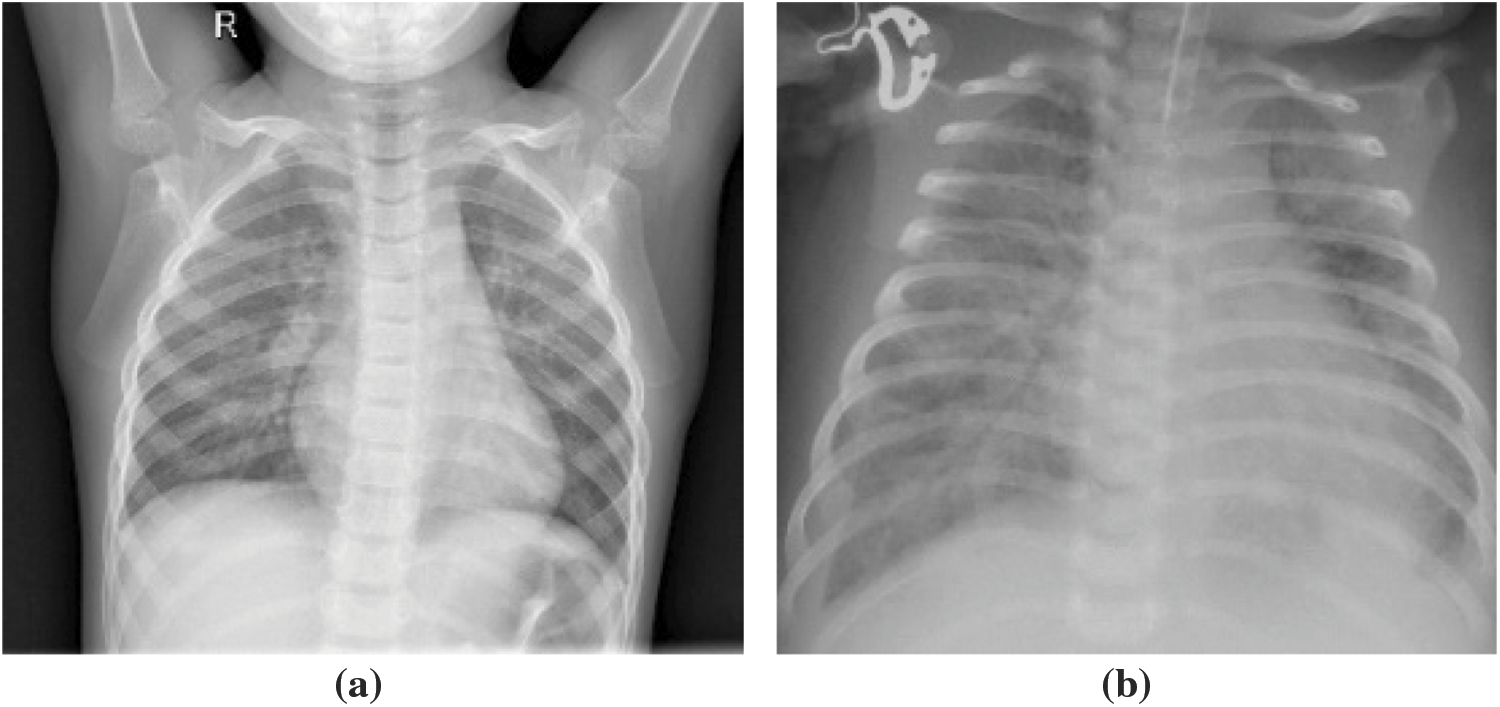

This dataset comprised chest X-ray images of lungs obtained from [29,30]. These images were selected from patients from Guangzhou Medical Center. The dataset is from an open dataset on the Internet. Generally, to obtain hospital images, they must be reviewed and approved by the patient before use. The image is in a standard image format (jpeg) and can be converted to a tensor format for use. The images were categorized into “normal” and “pneumonia” images (Fig. 10).

Figure 10: X-ray image of (a) normal person, (b) pneumonia person